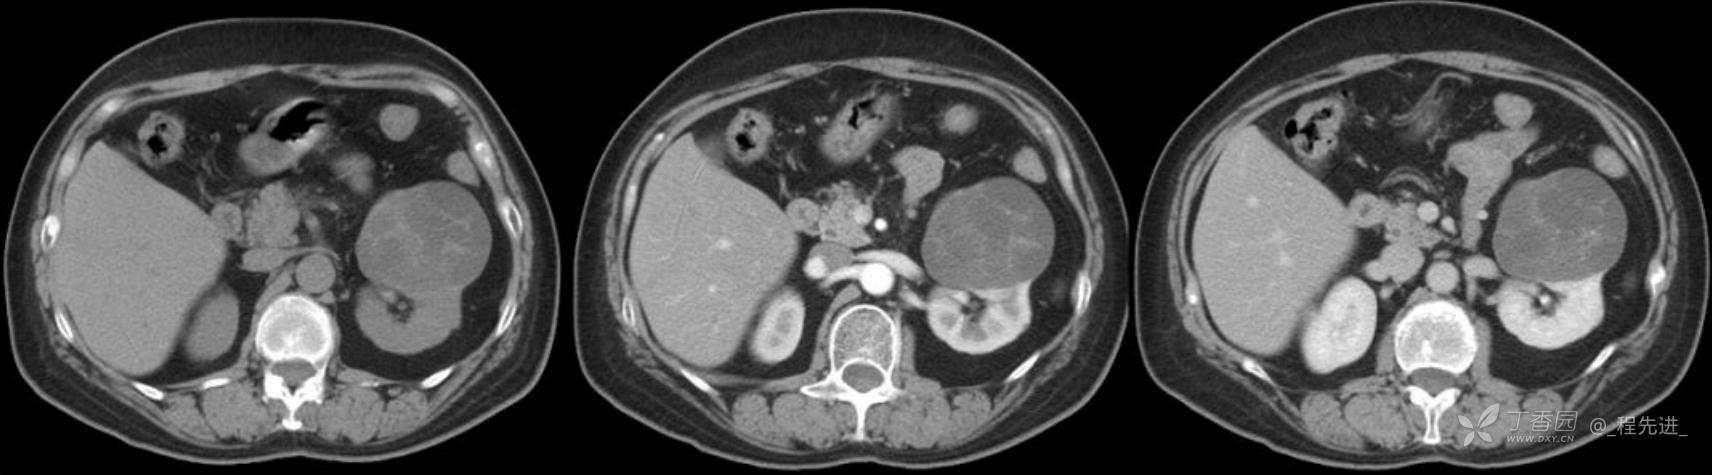

患者性别:女

患者年龄:53岁

简要病史:反复头昏、头痛5年,再发加重3月

辅助检查:无特殊,输血前检查、生化检查均正常

混合性上皮和间质肿瘤 (1)